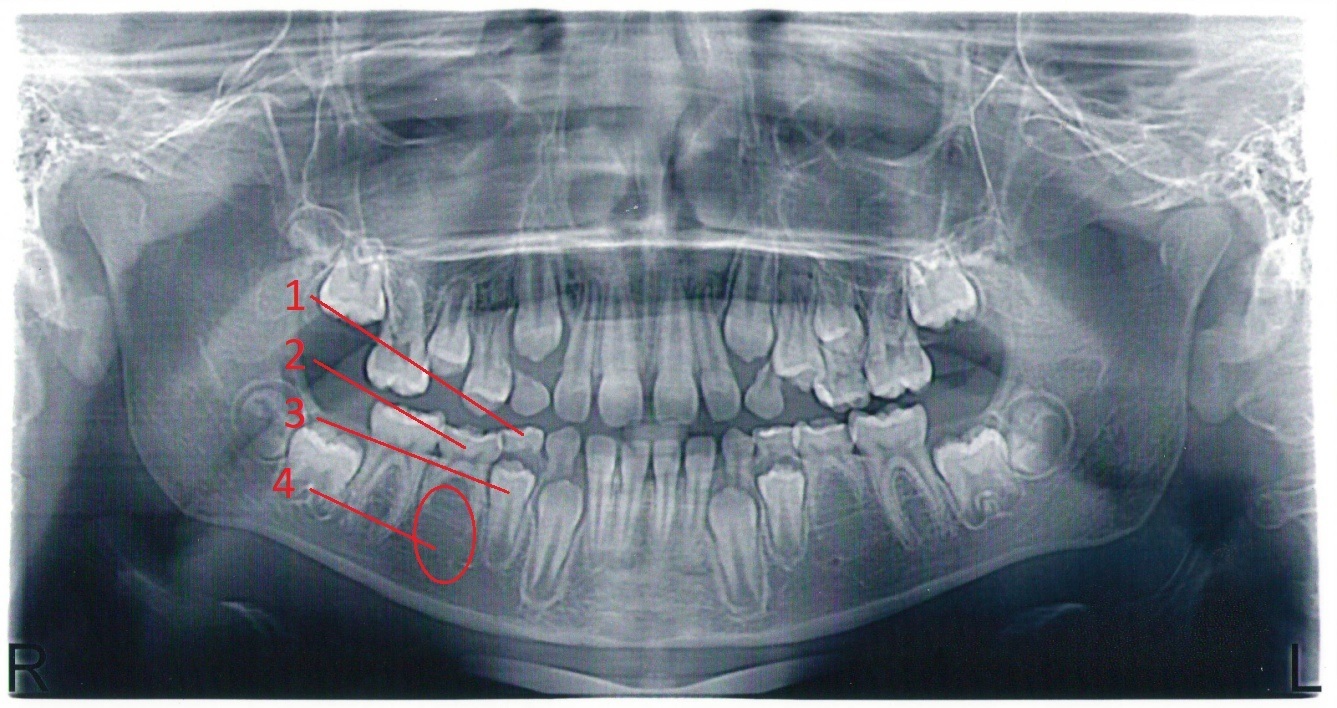

Снимок челюсти найденный в интернатах. На снимке цифрами обозначены:

1. Молочный первый моляр. Он же 4 зуб.

2. Молочный второй моляр, он же 5 зуб.

3. Постоянный первый премоляр, он же 4 зуб, который растет на смену молочному 4 зубу и уже почти его выпихнул. Корни молочного полностью рассосались

4. Область, где должен был быть второй постоянный премоляр, но его там нет. Соответственно у молочного моляра есть корни (многие считают что у молочных зубов нет корней, есть и еще какие! И этот моляр имеет все шансы достоять до 35 лет.

Иллюстрация к комментарию